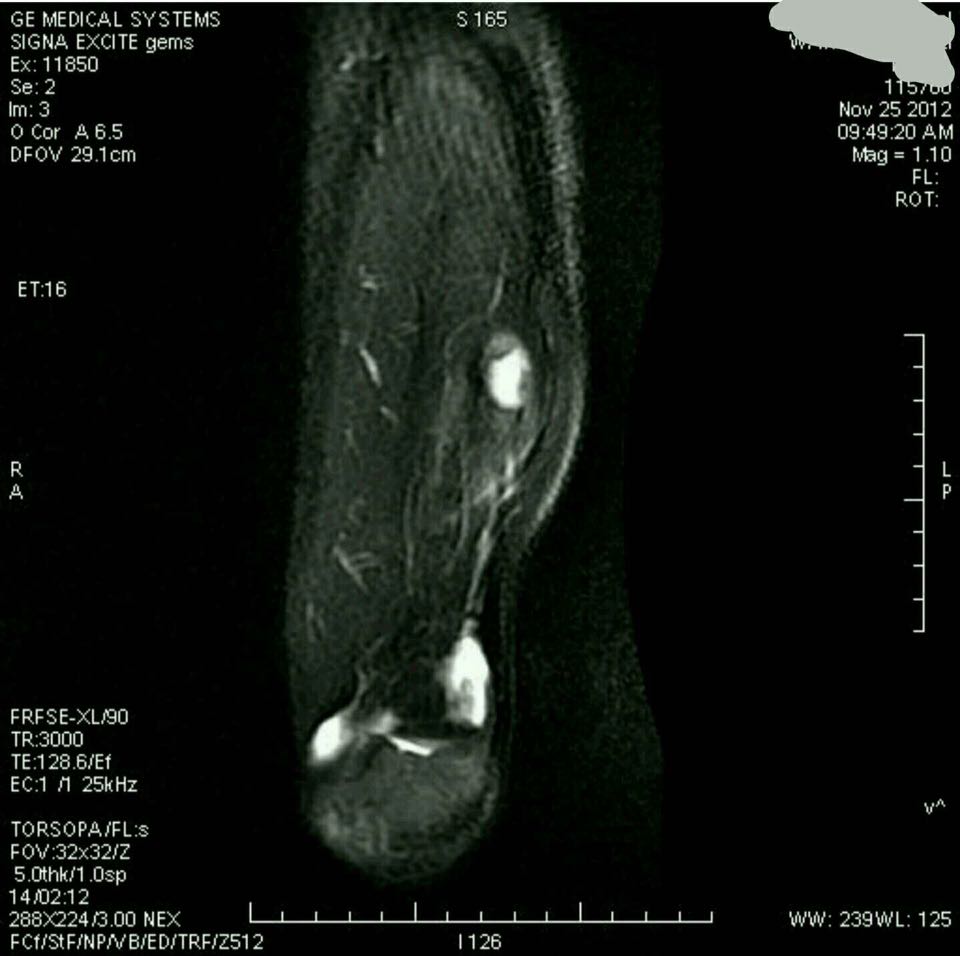

左膝X线片示:髌骨周围软组织密度增高,髌骨形态异常,呈溶骨性破坏,骨皮质膨胀、变薄,呈肥皂泡样改变,无骨膜反应(图1a,1b);髌骨CT显示:膨胀性溶骨性破坏,骨皮质变薄、变形。